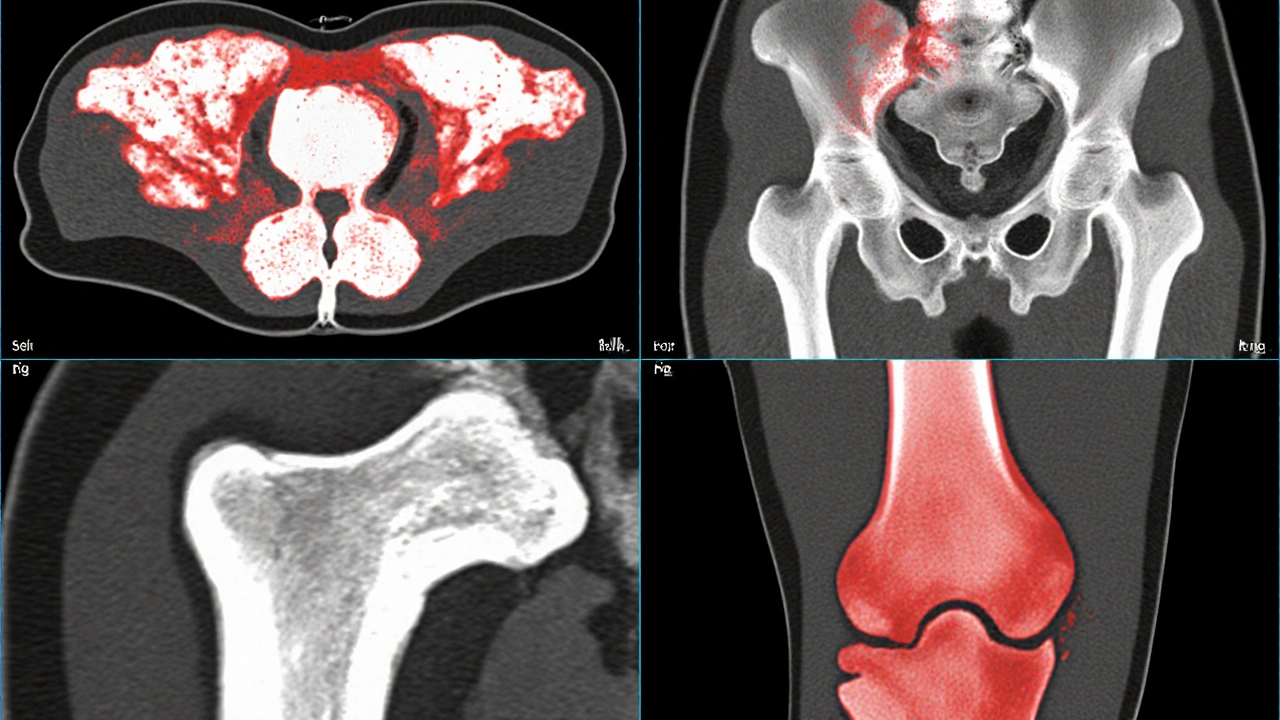

- Imaging: X‑ray, CT, MRI, and bone scintigraphy. PET/CT with ^18F‑FDG is increasingly used for whole‑body staging.

Bone mineral density (BMD) drops dramatically in metastatic zones. Studies measuring BMD by DXA in breast cancer patients with bone mets show a 30‑40% reduction compared with age‑matched controls.

Fracture risk isn’t just about density; it’s also about architecture. Micro‑CT analyses reveal that metastatic bone has thinner trabeculae and larger cortical pores, both of which undermine mechanical strength.

- Pathological fractures of the femur, spine, or pelvis-often requiring surgery.